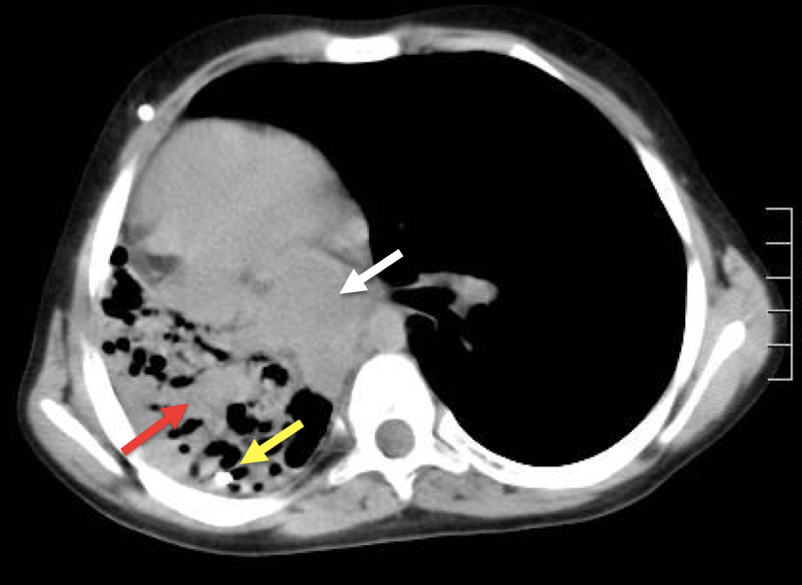

Ingresó a nuestra Institución, sin clínica neurológica progresiva, a través de la consulta ambulatoria con el Servicio de Neumonología. Se realizó una radiografía de tórax de rutina (Figura 1) y se completó estudios con Tomografía de tórax (Figura 2), en la que se evidenciaba migración intratorácica transdifragmatica del catéter distal de la DVP e infiltrado pulmonar derecho, asociado a fibrosis y retracción mediastínica. Se realizó Tomografía cerebral, evidenciando mayor dilatación ventricular en comparación al estudio previo. El paciente ingresó a quirófano para revisión del sistema valvular y recolocación de catéter distal en cavidad peritoneal. Evolucionó favorablemente y fue dado de alta con controles ambulatorios. Cinco meses después, el Servicio de Cirugía General realizó una neumonectomía estándar derecha, a través de toracotomía posterolateral, debido a la extensa destrucción pulmonar. A la inspección quirúrgica, no se observó lesión diafragmática. El informe histopatológico de la muestra evidenció fibrosis, bronquiectasias e infiltrado inflamatorio crónico con evidencia de sobreinfección aguda (Figura 3).

Figura 2: Tomografía computarizada del tórax del Caso 1, que muestra el catéter distal migrado dentro del parénquima pulmonar derecho. Nótese la hiperdensidad patológica del tejido pulmonar (flecha roja) con el catéter distal migrado (flecha amarilla) y la retracción y desplazamiento del mediastino (flecha blanca).